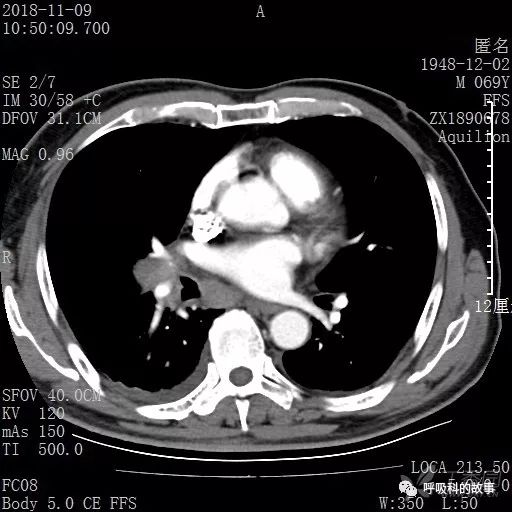

胸部增强CT示右肺门占位伴远端阻塞性肺炎,纵膈、右肺门、右侧颈根部、右侧腋下及肝门部肿大淋巴结。两侧胸腔少量积液。

纵隔窗的增强CT

肺窗CT